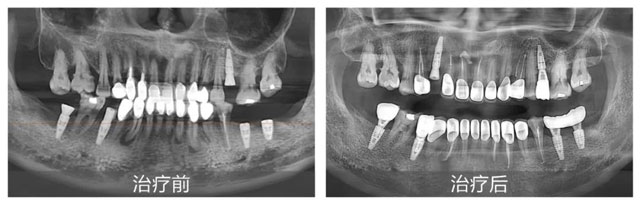

李女士治療前后口內(nèi)全景片

新橋口腔成都衣冠廟院區(qū)口腔全科醫(yī)生劉宇為李女士進行了全面細致的面診,結合全景片、CBCT、口內(nèi)檢查,再加上耐心的問診,劉宇判斷出李女士復雜的口腔狀況:四環(huán)素牙、死髓牙相關性基牙顏色異常,牙冠邊緣牙體齲壞發(fā)黑變色,嚴重影響美觀;存在牙齒長期齲壞、牙神經(jīng)發(fā)炎、根尖發(fā)炎等問題;而牙齦紅腫出血、松散萎縮等牙周病問題更是讓她的口腔狀況雪上加霜。

李女士的口腔狀況較為復雜,所涉問題橫跨多個學科領域,修復治療、口內(nèi)治療、牙周治療需同時兼顧,這無疑是對醫(yī)生綜合能力的考驗。劉宇醫(yī)生憑借豐富的臨床經(jīng)驗,為李女士量身定制了一套全面、科學的整體治療方案。首先通過根管治療消除根尖炎癥,針對牙周病展開系統(tǒng)治療,待牙齦恢復健康狀態(tài)后,最后制作新的牙冠,全方位改善牙齒的外觀與功能。此外,在牙齦恢復至健康狀態(tài)前,考慮到李女士的日常用牙需求,劉醫(yī)生特意為她安裝了臨時牙冠,讓李女士在治療期間也能正常飲食,盡可能減少治療對生活的影響。